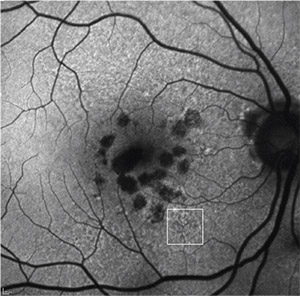

| Figure 5. Fundus autofluorescence of multifocal geographic atrophy presenting as multiple discrete foci of retinal pigment epithelium atrophy, which carries a risk of geographic atrophy progression. Reticular pseudodrusen is also visible (white square). |

Progression rates in eyes with the banded and diffuse FAF pattern were significantly higher compared to eyes without FAF abnormalities or with focal FAF patterns (Figure 4). An additional diffuse trickling pattern exhibited an even greater progression of GA when compared to the other diffuse types.26 Furthermore, the presence of multifocal atrophic spots and extrafoveal lesions were biomarkers predictive of GA progression (Figure 5).27